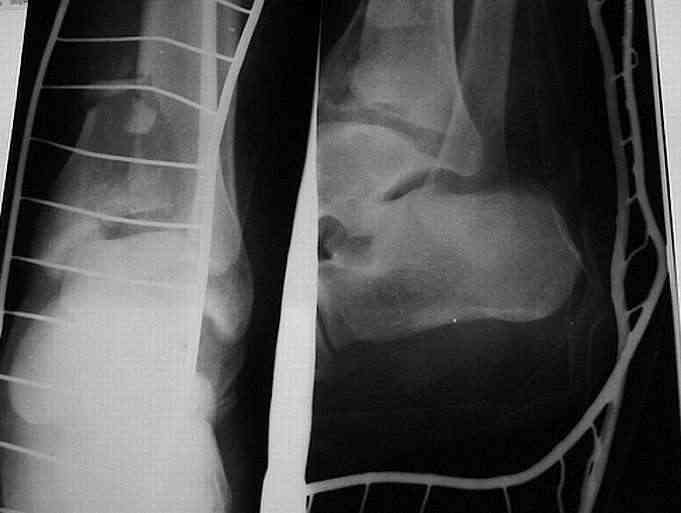

Здравствуйте, коллеги.Больной 26 лет, в 2004 году попал ко мне с диагнозом:синтезированный в аппарате Илизарова неполный внутрисуставной оскольчатый перелом дистального метафиза левой большеберцовой кости со смещением; выраженный остеопороз; множественное спицевое нагноение. Несостоятельность фиксации (костные отломки буквально "елозили" по спицам, несмотря наналичие упорных площадок).

Мной был демонтирован АВФ, удалены все спицы. Больной некоторое время лечился консервативно (шина Белера, антибиотики, перевязки). По заживлению и купировании гнойно-воспалительного процесса была произведена осткрытая репозиция, накостный остеосинтез 1/3 трубчатой пластиной.Такой вариант был принят из-за жуткого остеопороза и отказом больного от предложенного артродезирования голеностопного сустава сразу. Послеоперационный период без особенностей. Через год, больной пришел на осмотр на своих двоих, без дополнительной опоры, с жалобами на боли приходьбе в обл. г/стопа и с желанием замкнуть сустав. В операционной столкнулся с неожиданной проблемой по удалению пластины, она была глубоко вмурована в толщу склерозированного метафиза на глубину 1.5 см; удалить не рискнул (считал, что металл помешает в ходе реконструкции и требуется его удаление).